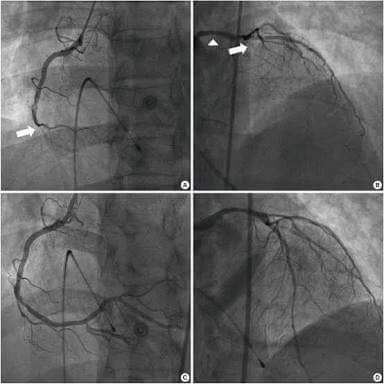

Kasus ini bukan kasus fiktif, hanya saja settingnya disesuaikan dengan realitas di Indonesia. Kejadian yang sama menimpa pasien berusia 39 tahun yang hanya memiliki faktor risiko merokok di KOREA SELATAN. Tapi disana, karena hampir setiap RS di kota besar memiliki fasilitas Cath Lab yang sanggup melakukan Primary PCI maka tindakan live-saving ini dapat dikerjakan dalam waktu yang relatif cepat. Dibawah bisa dilihat adanya sumbatan pada kedua arteri koroner yang kemudian sukses dibuka melalui tindakan Primary PCI. Pasiennya tertolong tanpa komplikasi yang berarti. Kasus aslinya bisa dibaca di http://goo.gl/MeFzPD